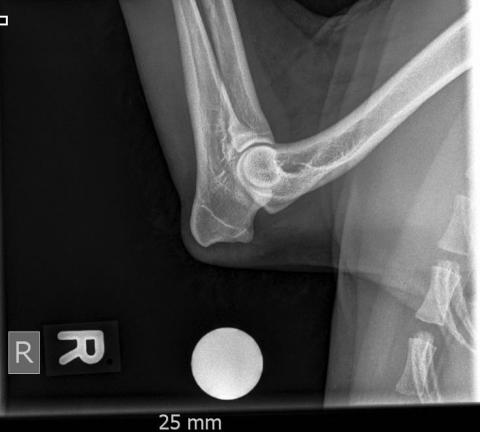

• ED Abklärungen

• Frakturbeurteilung